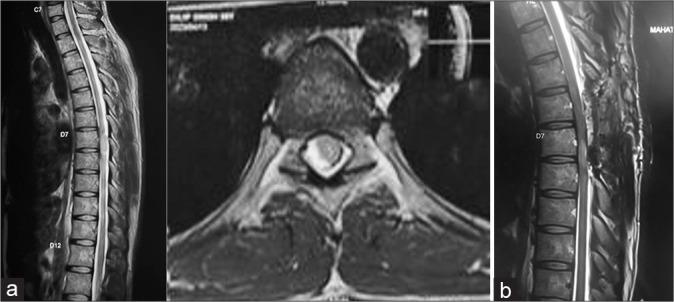

The age range, gender distribution, presentation, histopathology, and tumor characteristics were analyzed. The histopathological outcomes of the study were as follows: 56 cases of schwannoma, 37 cases of meningiomas, 16 patients of neurofibroma, six cases of epidermoid cyst, five cases each of ependymoma and dermoid cyst, three cases of arachnoid cyst, two cases of metastasis, and one case of paraganglioma. Pain was the most common symptom (38.5%), followed by weakness in limbs (31.5%), paresthesia/numbness (22.3%), and sphincter disturbance (7.7%). Complete total resection was seen in 93% of cases, with 7% undergoing subtotal excision. The complications encountered were - four cases of surgical site infection and one case each of cerebrospinal fluid leak, pseudomeningocele, and epidural hematoma. In our series, 49.3% of patients had significantly good improvement in functional outcomes as per improvement in Frankel score, and 43% of patients had good functional improvement. Significant functional improvement was noted at immediate postoperative follow-up, 2-week follow-up, and six-month follow-up periods. Reoccurrence was seen in 7 cases (5.4%). The DPS score mean values showed a significant decrease over the follow-up duration as compared to preoperative mean values. Significantly poor outcome was seen in IDEM tumours present anteriorly.

The IDEM tumors are usually benign and are readily detected by contrast-enhanced magnetic resonance imaging scans. These have variable functional outcomes in different centers. Assessing this functional outcome is an essential aspect of managing IDEM spinal tumors. It was observed through our study that the ventral location of the tumor, thoracic tumors, and poor preoperative neurological status of the patient correspond with poorer postoperative functional outcomes. Furthermore, a significant decrease in the pain symptoms with improvement of Frankel score was seen postoperatively, thus this being suggestive of a significant improvement of functional outcome after surgery. This study helps to conclude that the morbidity associated with the resection of IDEM tumors is not as significant as originally thought to be.